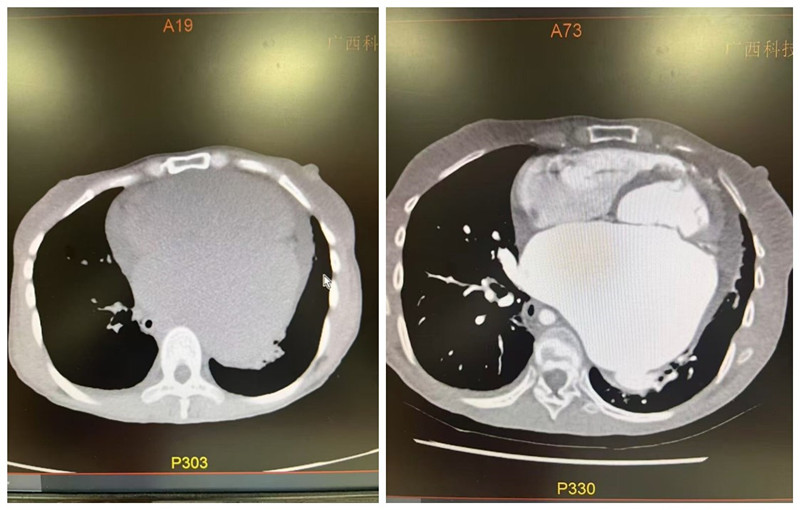

胸闷、气促、反复发热……44岁的覃先生被多重致命疾病缠身。面对感染性心内膜炎、双肺感染、右室流出道狭窄等多重“拦路虎”,我院胸心血管外科团队迎难而上,凭借精湛技术,在体外循环(CPB)下成功实施“室间隔缺损修补术+右室流出道疏通术+三尖瓣成形术”,为患者重启“生命之门”!

张先生因“反复发热、胸闷气促半月”紧急入院,经检查确诊为“感染性心内膜炎”,心脏超声提示:室间隔缺损(心脏“漏洞”导致血液异常分流);右室壁异常增厚,右室流出道严重狭窄(血流通道受阻,心脏“不堪重负”);三尖瓣重度关闭不全(心脏阀门失灵,加重心力衰竭);双肺严重感染(呼吸功能急剧恶化)。感染持续侵蚀心脏结构,心肺功能濒临崩溃,若不及时手术,患者将面临心衰、多器官衰竭甚至猝死的风险。心脏结构复杂,室间隔缺损位置特殊,右室流出道因肌肉异常增厚严重狭窄,需在修复缺损的同时精准疏通“生命通道”,并重塑三尖瓣功能。

手术历时6小时,顺利完成。术后心脏超声显示:室间隔缺损完全闭合,右室流出道血流畅通,三尖瓣启闭良好,心脏功能显著改善!